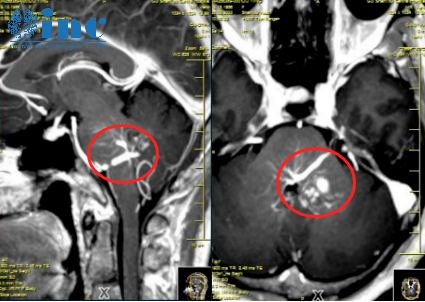

晓玲术前术后影像对比

桥脑海绵状血管瘤病变位置,血管病变不邻接桥脑表面,但它单侧移动周围的固有结构,包括外展神经和面神经。